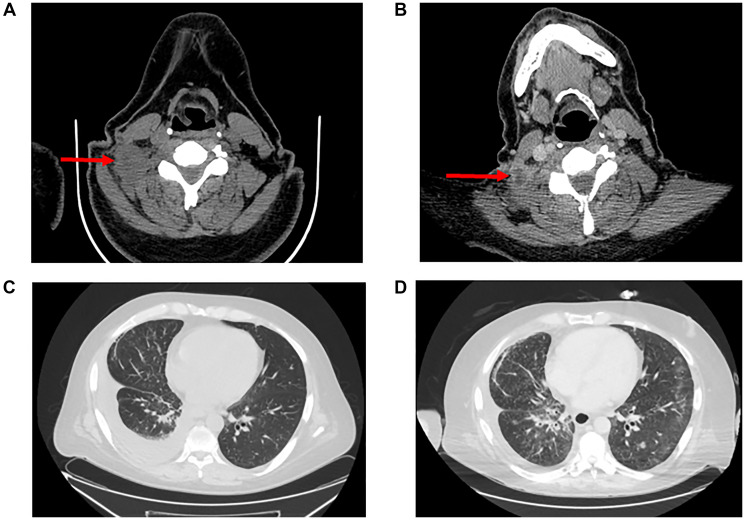

ROS1 and RET fusions are targetable mutations that occur in a subset of patients with non-small cell lung cancer (NSCLC). ROS1 and RET have been understood to be independent oncogenic drivers which do not co-occur with other common tyrosine kinase receptor mutations except in the acquired resistance setting. Here we present a case of a patient with stage IV CD-74-ROS1 fusion NSCLC discovered initially with RNA next generation sequencing (NGS) who acquired resistance to lorlatinib after 6 months on therapy through a novel RUFY1-RET fusion, detected only through RNA NGS. Combination therapy targeting RET and ROS1 using pralsetinib and lorlatinib achieved a partial response with limited durability of only four months. This is the first reported case of a RET fusion as a potential mechanism of resistance to lorlatinib, it identifies a novel RET fusion partner, and it emphasizes the importance of testing for acquired resistance mutations with both DNA and RNA at the time of progression in patients with targetable oncogenic drivers.